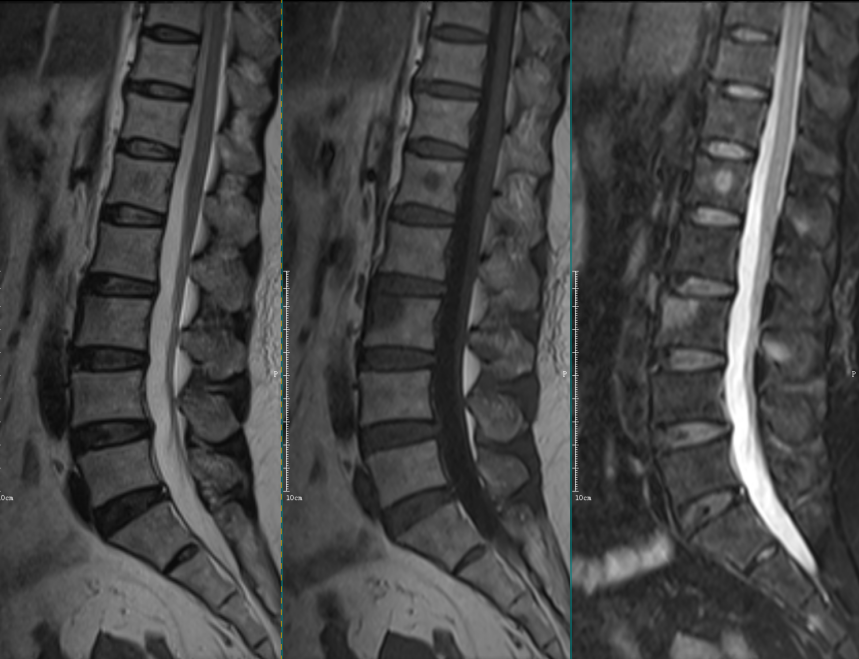

Modic Ⅰ型:

L4-5椎间盘上下缘见条带状异常信号,T1WI低信号,T2WI高信号,STIR序列高信号。

L5-S1椎间盘上下缘见条带状异常信号,T1WI低信号,T2WI高信号,STIR序列高信号。